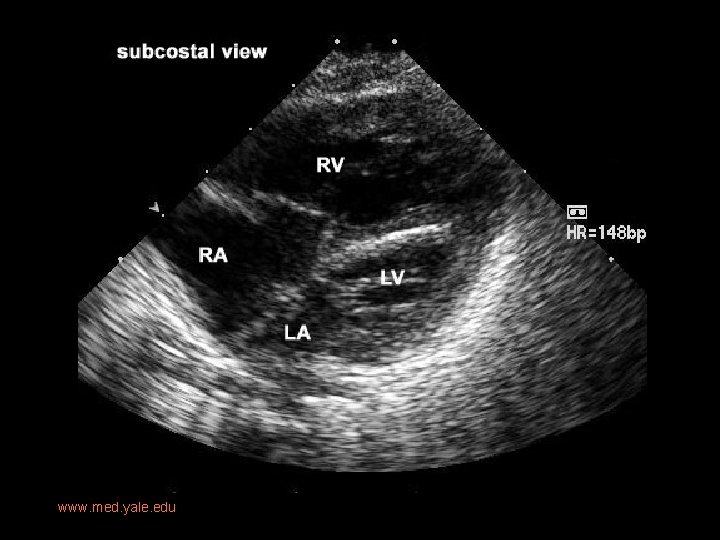

Imaging • Prenatal US: diastolic flow reversal in extremely narrow ascending Ao is diagnostic for HLHS. • Real-time echo: § sm, thick walled LV, sm MV w/restricted motion § Dilated RH/PA, lg PDA § Sm ascending Ao • CXR: § Moderate-marked CM § Globular cardiac silhouette suggesting combined chamber enlargement § PV congestion with interstitial/pleural fluid

www. med. yale. edu